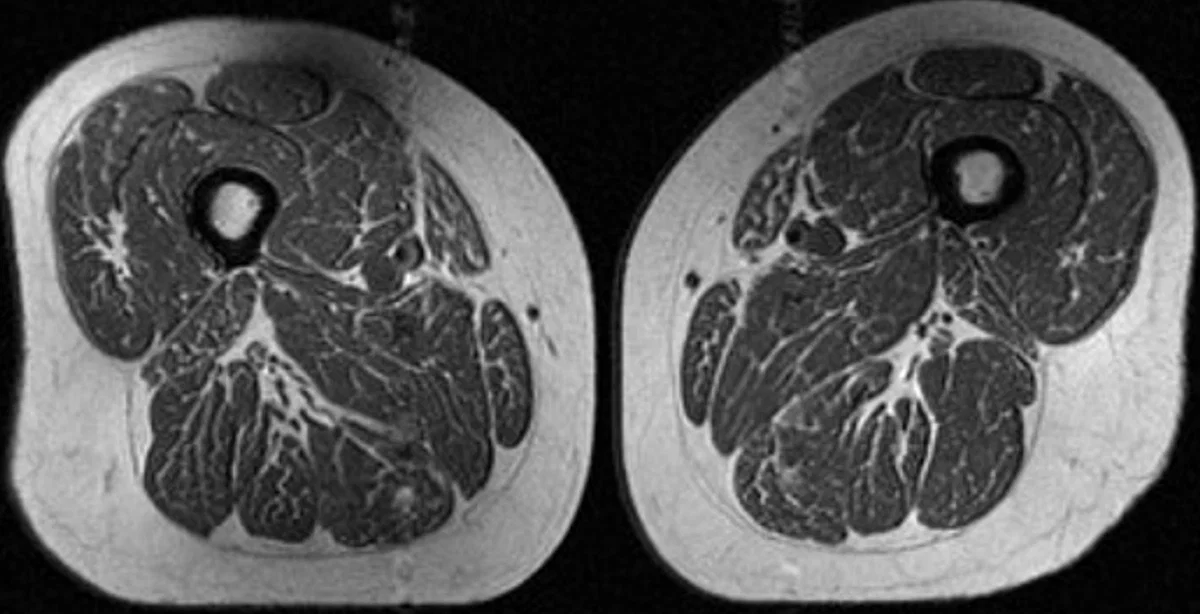

When a 62-year-old woman’s MRI scan revealed thigh muscles that looked eerily like a marbled steak, it wasn’t just the unusual appearance that caught attention, but what it signified. Her diet was a staggering 87% ultraprocessed foods. This image is more than just an oddity; it represents a disturbing trend in modern diets linked to severe health risks, especially in relation to muscle quality and joint health. This study is a wake-up call about the hidden consequences of ultraprocessed foods, showing that the effects go beyond weight gain and obesity.

In the study published in Radiology, Dr. Akkaya and her team used MRI scans to analyze the muscle quality of participants at risk for knee osteoarthritis. The results were startling. A woman consuming 87% of her calories from ultraprocessed foods had significant fat infiltration in her thigh muscles. This fat wasn’t just sitting around the muscles—it was embedded between muscle fibers, making them weaker and less efficient. This phenomenon, referred to as “fat marbling,” is closely linked to muscle degeneration, which can compromise mobility and stability.